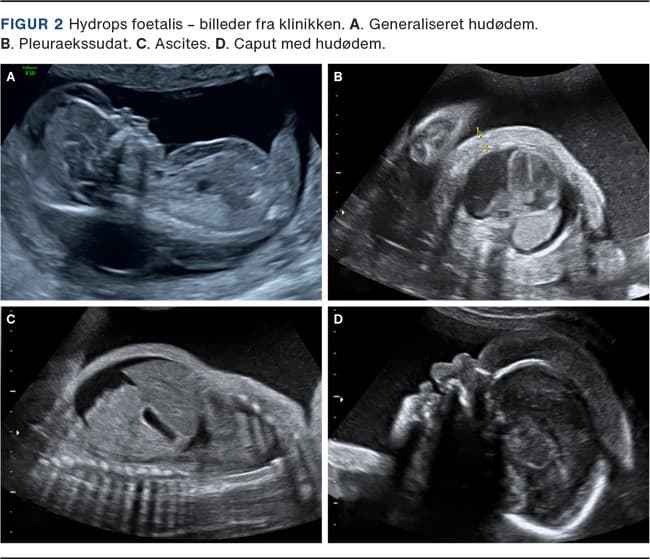

HF diagnosticeres med ultralydskanning ved fund af to eller flere væskefyldte kaviteter (ascites, pleuraekssudat, perikardieekssudat og/eller hudødem) (Figur 2). Ascites ses i tidligt stadie som en væskebræmme i den abdominale kavitet, og ved tiltagende hydrops vil tarmene fremstå som et lille, samlet konglomerat i et stort væskefyldt abdomen [17]. Pleuraekssudat ses som en væskebræmme i thorax omkring lungerne. Ved tiltagende pleuraekssudat komprimeres lungerne, og persisterende pleuraekssudat kan derfor medføre kompromitteret lungeudvikling og pulmonal hypoplasi [18]. Perikardievæske ses normalt som en fysiologisk lille væskebræmme omkring hjertet, men ved en væskebræmme på mere end 2 mm tyder det ofte på perikardieekssudat med en patofysiologisk ætiologi [17, 19]. Hudødem er et sent tegn på HF og ses som en subkutan vævstykkelse på 5-6 mm især på thorax eller på skalpen og bør ikke forveksles med subkutant fedt [17].